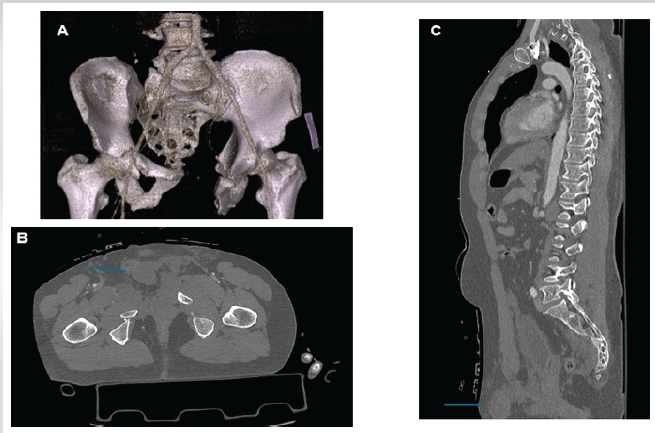

Two male patients (aged 51 and 40) were admitted following high-energy motor vehicle collisions in 2021 and 2024. Each sustained unstable pelvic ring injuries: One with a Tile C2 (AO 61-C2), and the other with a Tile B3 (AO 61-B3) fracture pattern. Time from injury to surgery was 48 h in both cases. Pre-operative computed tomography (CT) scan revealed right testicular dislocation into the pelvic cavity, anterior to the bladder, identifiable in axial and sagittal views (Figs. 1 and 2). Physical examination noted hemiscrotal asymmetry, but due to the patients’ polytrauma context, findings were not initially prioritized.

Figure 2: Preoperative computed tomography images from Case 2. (a) Three-dimensional reconstruction of the pelvic ring injury. (b) Coronal view showing intrapelvic displacement of the right testicle (blue arrow). (c) Sagittal view confirming the same finding (blue arrow).